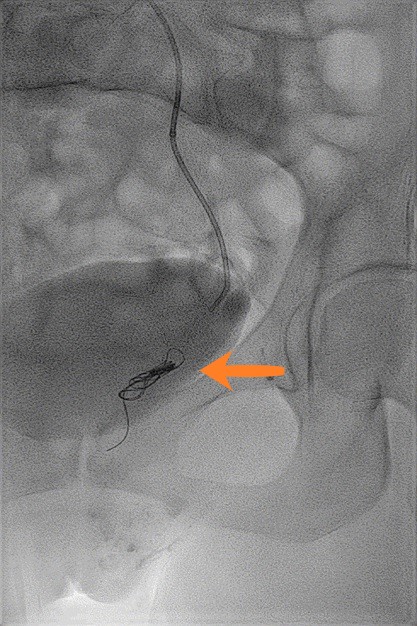

Exemple d'images d'embolisation réalisée dans le service.

Deuxième image, à droite : phase de traitement avec coils d'embolisation (flèche orange) en place dans la veine gonadique gauche, permettant son occlusion.